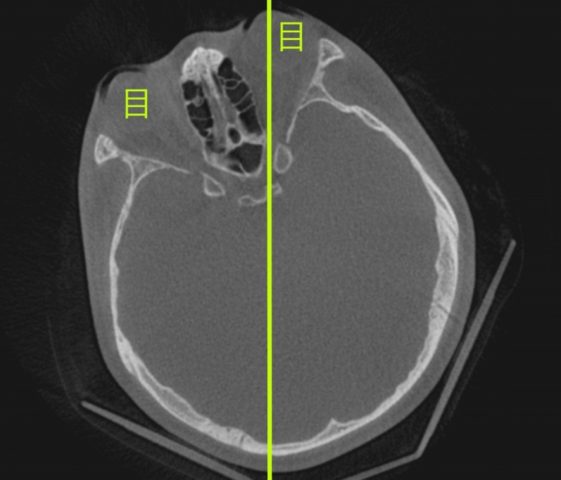

頬骨_痛い時_頬骨の高さの水平線

上のラインで、顔を輪切りにすると。

頬骨_痛い時_頬骨と上顎洞

CT像は、こうなります。

頬骨の裏には、

上顎洞という空洞(副鼻腔)があります。

頬骨が痛い事は、

上顎洞炎(副鼻腔炎)と、

関係が近いと言えます。